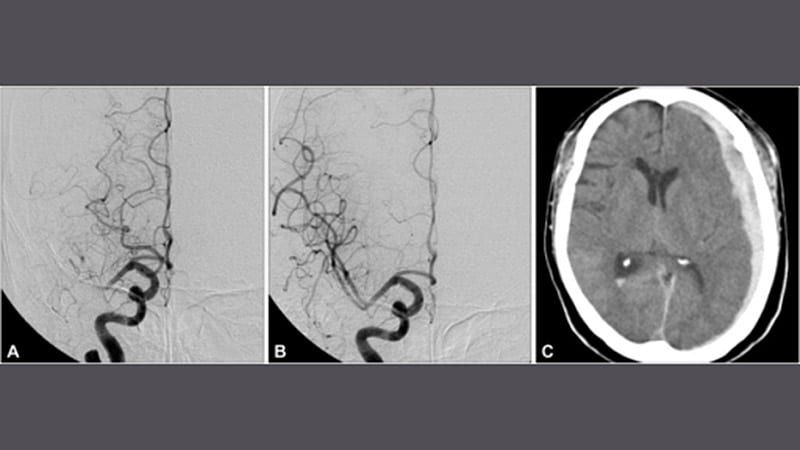

Endovascular Therapy Benefits Large Infarction: ANGEL-ASPECTA new study provides evidence for better functional recovery after endovascular therapy from a population of large-infarction

strokes that could contribute to changing clinical practice.